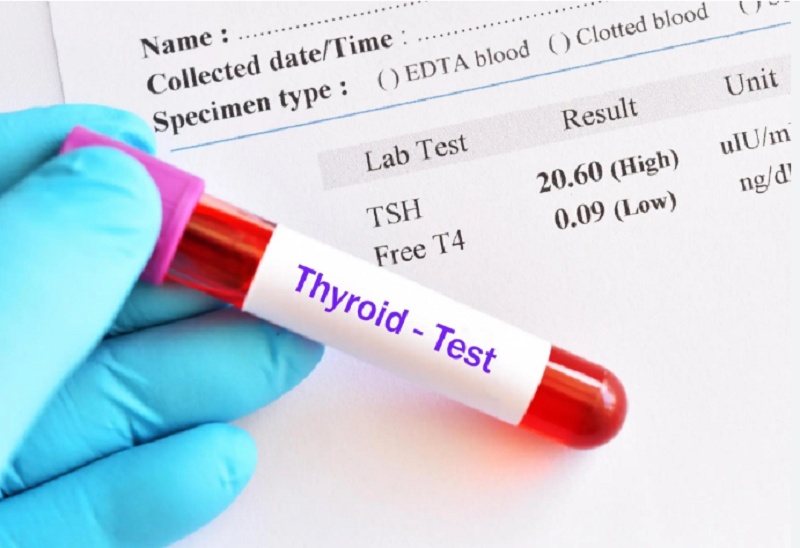

Ngoài ra, có những trường hợp T3 tổng bình thường nhưng triệu chứng tuyến giáp vẫn rõ rệt. Điều này có thể xảy ra khi Free T3 thấp do rối loạn chuyển đổi T4 → T3 hoặc bất thường trong vận chuyển hormone. Vì vậy, để đánh giá chính xác chức năng tuyến giáp, cần xem xét đồng thời bộ ba chỉ số TSH – Free T4 – Free T3 thay vì chỉ dựa vào T3 đơn lẻ.

Tại sao bạn cần xét nghiệm triiodothyronine hormone thường xuyên?

Xét nghiệm triiodothyronine hormone định kỳ không chỉ dành cho những người đã có bệnh tuyến giáp mà còn rất cần thiết đối với những ai có nguy cơ tiềm ẩn hoặc gặp các triệu chứng mơ hồ, giúp:

- Phát hiện bất thường hormone sớm: Giúp nhận diện rối loạn tuyến giáp trước khi triệu chứng rõ ràng, tránh nhầm với stress, thiếu ngủ hoặc rối loạn tiêu hóa.

- Giảm nguy cơ biến chứng tim mạch – chuyển hóa: T3 cao hoặc thấp kéo dài ảnh hưởng đến nhịp tim, huyết áp và mỡ máu.

- Đánh giá khả năng chuyển đổi T4 → T3: Phát hiện tình trạng Free T3 thấp dù T4 bình thường, đặc biệt ở người có bệnh mạn tính như tiểu đường, béo phì, gan nhiễm mỡ.

Hỗ trợ điều chỉnh thuốc tuyến giáp: Theo dõi Free T3 giúp bác sĩ tối ưu liều levothyroxine, tránh quá liều (gây hồi hộp, mất ngủ) hoặc thiếu liều (gây tăng cân, mệt mỏi). - Theo dõi thay đổi hormone theo từng giai đoạn: Phụ nữ mang thai, sau sinh, tiền mãn kinh hoặc người trên 50 tuổi dễ có biến động hormone và giảm chuyển hóa.

Theo một nghiên cứu năm 2021 đăng trên Frontiers in Endocrinology, những người xét nghiệm tuyến giáp đều đặn mỗi 6–12 tháng có khả năng phát hiện sớm bất thường T3 cao hơn 35% so với những người chỉ xét nghiệm khi có triệu chứng. Nhờ đó, họ giảm rõ rệt nguy cơ cường giáp tiềm ẩn và rối loạn nhịp tim liên quan đến bất thường hormone tuyến giáp.